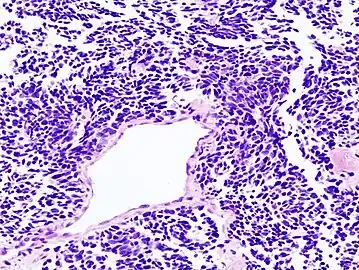

Small-cell carcinoma is an undifferentiated neoplasm composed of primitive-appearing cells. As the name implies, the cells in small-cell carcinomas are smaller than normal cells, and barely have room for any cytoplasm. Some researchers identify this as a failure in the mechanism that controls the size of the cells.[43]

Lung cancer is the leading cause of cancer-related deaths worldwide, accounting for the highest mortality rates among both men and women. When associated with the lung, SCLC is sometimes called "oat cell carcinoma" due to the flat cell shape and scanty cytoplasm. Caution is required when diagnosing SCLC because small cell mesothelioma – an extremely rare subtype of lung cancer – can be mistaken for small cell lung cancer.[24]

It is thought to originate from neuroendocrine cells (APUD cells) in the bronchus called Feyrter cells (named for Friedrich Feyrter).[25] Hence, they express a variety of neuroendocrine markers, and may lead to ectopic production of hormones like ADH and ACTH that may result in paraneoplastic syndromes and Cushing's syndrome.[26] Approximately half of all individuals diagnosed with Lambert–Eaton myasthenic syndrome (LEMS) will eventually be found to have a small-cell carcinoma of the lung.[23]